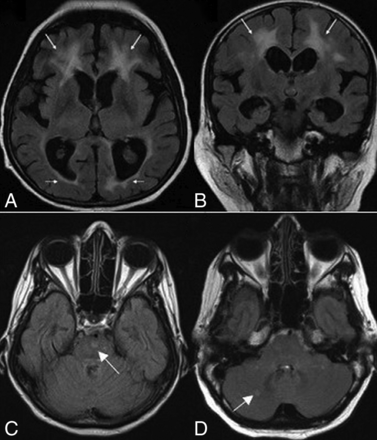

White matter abnormalities on T2-weighted and FLAIR images were seen in 18 patients (69.2%). These changes varied in terms of distribution and extension (Fig 3). Extension of WM changes was characterized by a periventricular and frontoparietal predominance (Fig 4A, -B). Involvement of other subcortical (basal ganglia, thalamus) and infratentorial structures was seen in 3 patients (11.5%) (Fig 4C, -D). Older age was associated with more severe white matter lesions (r = 0.71, P < .001). All white matter lesions were nonenhancing and spared the U-fibers.

Axial (A) and coronal (B) FLAIR MR images for case 24 show white matter changes with frontal predominance (arrows). Axial FLAIR images show signal intensities (arrows) involving the pons (C) in patient 19 and the cerebellum (D) in patient 26.